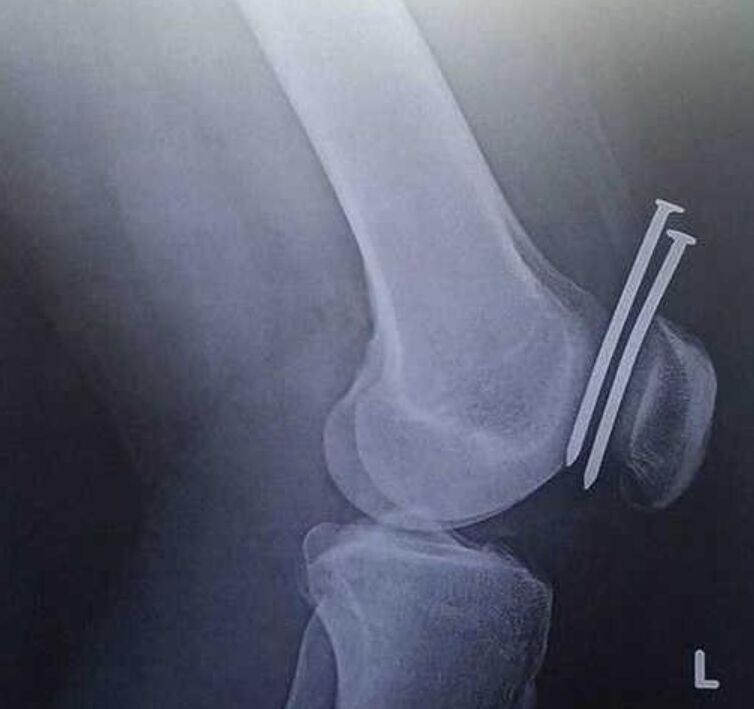

3、钉子刚好穿过膝盖骨及股骨间。不然以后可就瘸了!